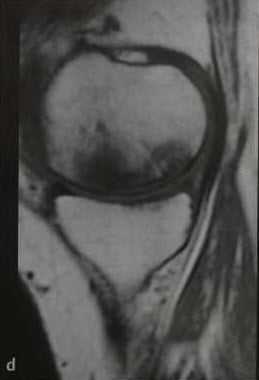

а-d Остеонекроз коленного сустава у женщины 65 лет. Внезапное возникновение болевого синдрома без травмы. Рентгенологическое исследование коленного сустава: (а) в прямой проекции, (b) в боковой проекции. Рентгенопрозрачные участки (стрелка) с окружающим склерозом, дегенеративными изменениями и уплощение суставных поверхностей.

(с), (d) МРТ. Фронтальное протонное плотно-взвешенное изображение с подавлением МР-сигнала от жировой ткани (с) и сагиттальное Т1 -взвешенное (d) изображение. Перифокальный отек и линейные субхондральные участки являются признаками стрессового перелома с дегенеративными изменениями в медиальном мениске.